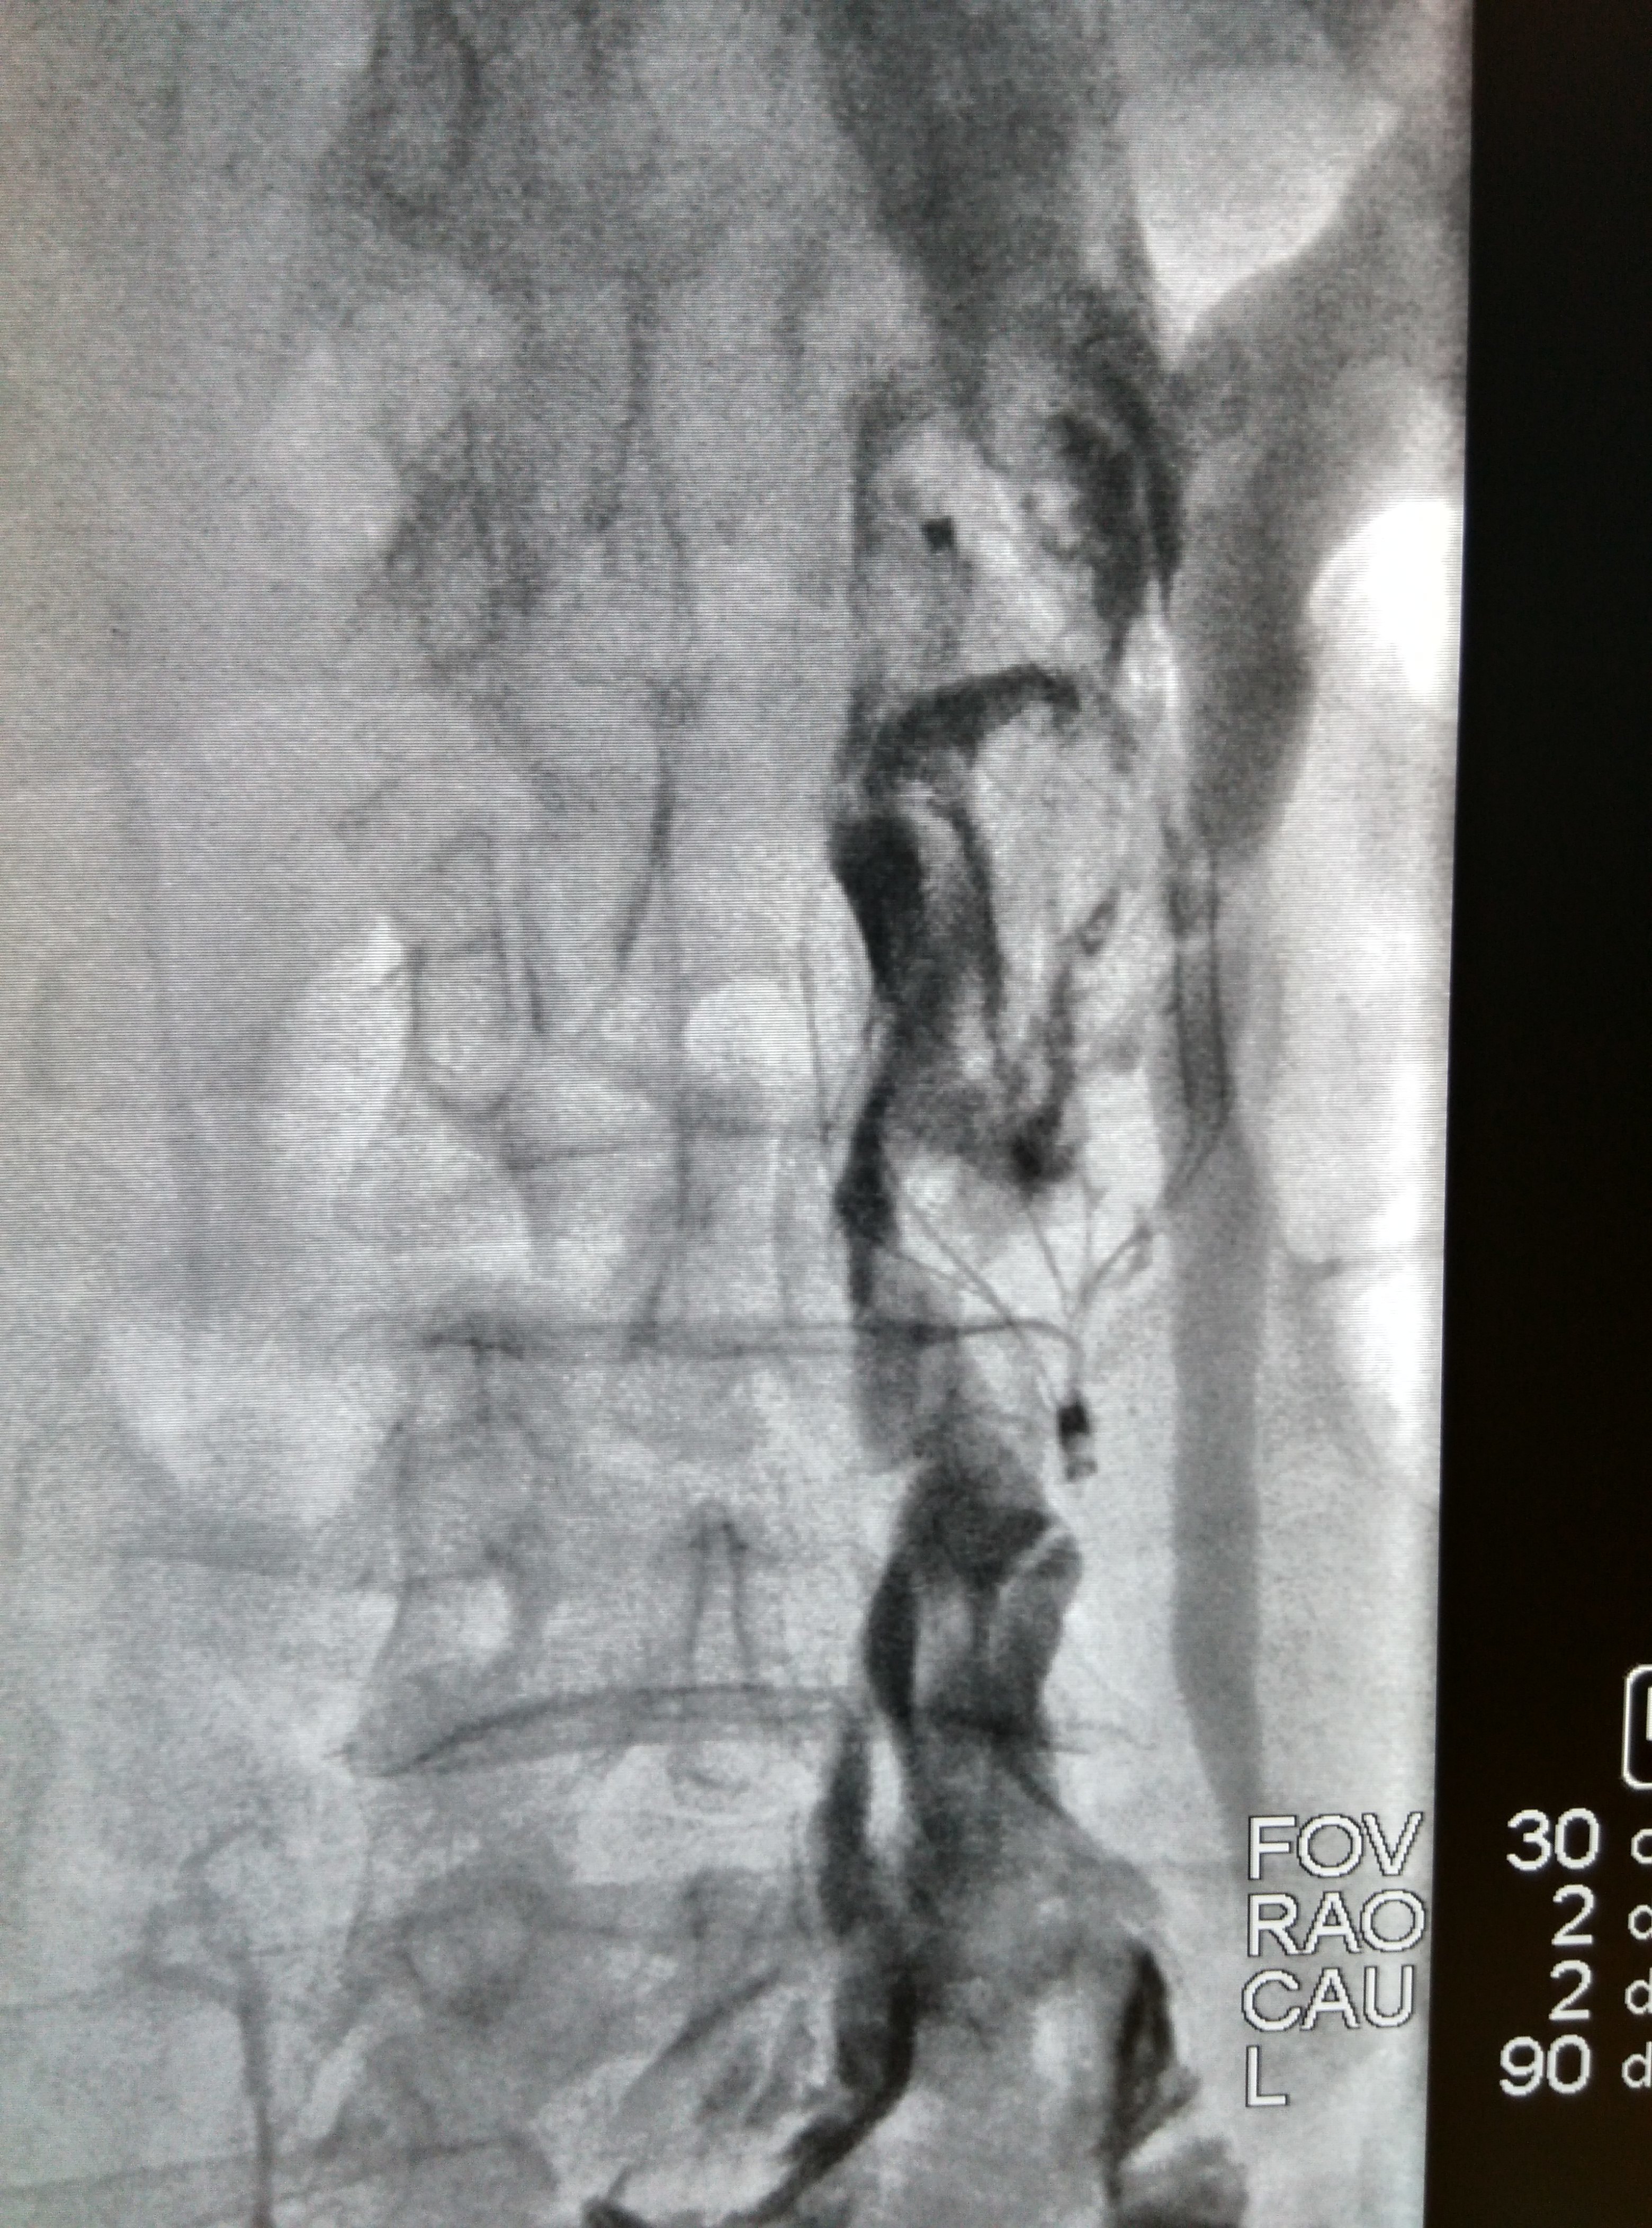

下肢静脉血栓与肺栓塞

3120x4208 - 2141KB - JPEG